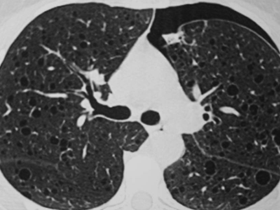

Pulmão com múltiplos cistos

Tomografia de tórax cistos difusos pelo pulmao